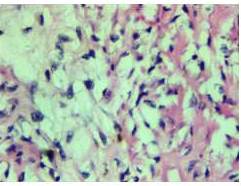

aciente femenina de 46 años, quien inicia enfermedad actual en 2014, cuando presenta aumento de volumen progresivo en mama izquierda, de 6 meses de evolución, al examen físico se observa un tumor sólido, blando, no adherido a planos profundos, móvil, que abarca la totalidad de la mama, de 30 cm x 30 cm, adenopatías axilares múltiples móviles, blandas, el examen ecosonográfico demuestra una imagen nodular sólida de gran tamaño 28 cm x 27 cm, hipoecoica, de contornos definidos, en la mamografía, mamas densas, se observan calcificaciones gruesas dispersas. La mama derecha era voluminosa, sin signos aparentes de lesiones. Se realizó una biopsia por aguja gruesa (BAG) con el hallazgo histológico de proliferación de componente mesenquimal y epitelial concluyendo como tumor filodes. Se realizó una mastectomía simple izquierda, evidenciando tumor de 20 cm x 20 cm que ocupa toda la mama izquierda, con red venosa en relieve con la piel; cuya evaluación histológica reportó un tumor filodes benigno (Figura 1-4) con bordes de resección negativos con márgenes amplios; la paciente continua en control, evidenciándose en el año 2016 una lesión tumoral en cuadrante superior interno (CSI) de la mama derecha, de 4 cm x3 cm, móvil, no doloroso, se solicitó ecografía y mamografía para evaluar la nueva lesión, sin embargo, la paciente se ausenta. Consulta de nuevo en 2017, al examen físico el tumor abarcaba la totalidad de la mama, de 20 cm x 23 cm, móvil no doloroso, con mama supernumeraria ipsilateral (Figura 5). En la mamografía, mama densa, se observaron calcificaciones gruesas dispersas, se realiza BAG con el diagnóstico de tumor estromal y epitelial (tumor bifásico); se realizó una mastectomía simple con resección de la mama supernumeraria, el diagnóstico definitivo fue tumor filodes borderline (Figura 6 - 8). Actualmente la paciente no presenta signos de enfermedad.

Macroscópicamente, los tumores más pequeños semejan fibroadenomas con un aspecto fibroso gris y blanco, mientras que los más grandes semejan sarcomas. Histológicamente se asemejan a elementos epiteliales y del mesenquima de un fibroadenoma, pero se diferencia por el potencial de crecimiento y celularidad del estroma (6,7,8).

Este tumor por su naturaleza, crece radialmente, comprime el parénquima mamario y crea una pseudocápsula a través de la cual sobresalen lengüetas. El examen del tejido conectivo en secciones múltiples es obligatorio, porque el filodes maligno puede estar presente solamente en una porción del tumor (6).

El diagnóstico diferencial debe establecerse con el fibroadenoma mediante criterios morfológicos. El tumor filodes benigno se caracteriza por una marcada hipercelularidad estromal y el maligno por una malignización del estroma con cambios metaplásicos (3,4).

La Organización Mundial de la Salud (OMS) los clasifica en tumores benignos, borderline, y malignos, según su comportamiento biológico de acuerdo a tres características histológicas: el patrón de crecimiento periférico, si es infiltrativo o expansivo, el índice mitótico del componente mesenquimático y las atipias nucleares.